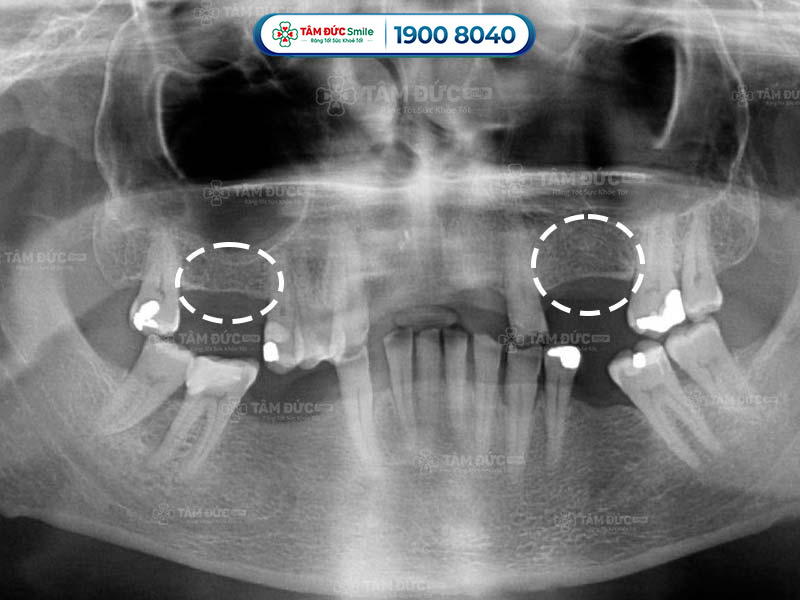

1.1. Quan sát dấu hiệu tiêu xương răng qua phim chụp X-Quang

Một trong những dấu hiệu tiêu xương răng rõ ràng nhất là hiện tượng hạ thấp của sàn xoang hàm. Sàn xoang hàm là một vách ngăn mỏng nằm giữa xoang hàm và xương ổ răng. Khi răng bị mất, lực nhai không còn tác động lên vùng xương ổ răng, làm cho xương ổ răng teo dần.

Trên phim chụp X-Quang, bác sĩ dễ dàng nhận thấy sự hạ thấp của sàn xoang hàm. Sự hạ thấp này được đánh giá bằng cách đo khoảng cách từ sàn xoang đến nướu răng.

Dấu hiệu tiêu xương răng qua phim X-Quang